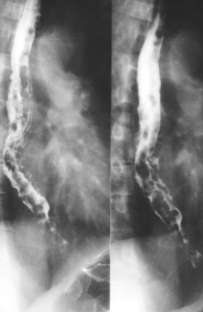

Une autre cas de

oesophagite caustique . La lesion etendue le long

2/3 superiere de oesophage . Image radiologique du

transit oesophagien en OAD |

Oesophagite caustique 1/3 moyen de

oesophage avec aspect lesionaire c'est imsage

stenose cicatricielle a bord lisse de perdre

elasticite ( fleche blanche ) |